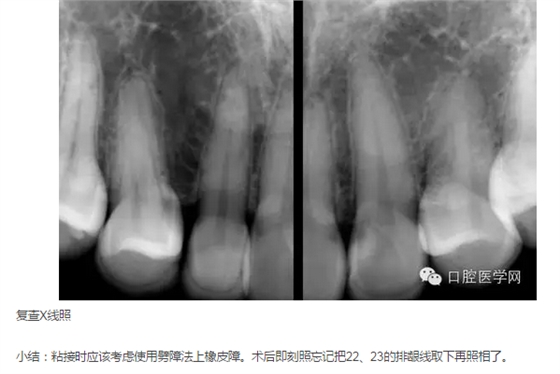

X線片示:未見(jiàn)13、23;14、12-22、24牙根未見(jiàn)明顯異常,牙槽骨約在根長(zhǎng)2/3水平,牙槽嵴頂影像清晰。48、38近中水平阻生向分別抵于47、37遠(yuǎn)中。

2015年3月26日:檢查,咨詢。拍照(見(jiàn)圖1-9),拍X線片,取分析模型。